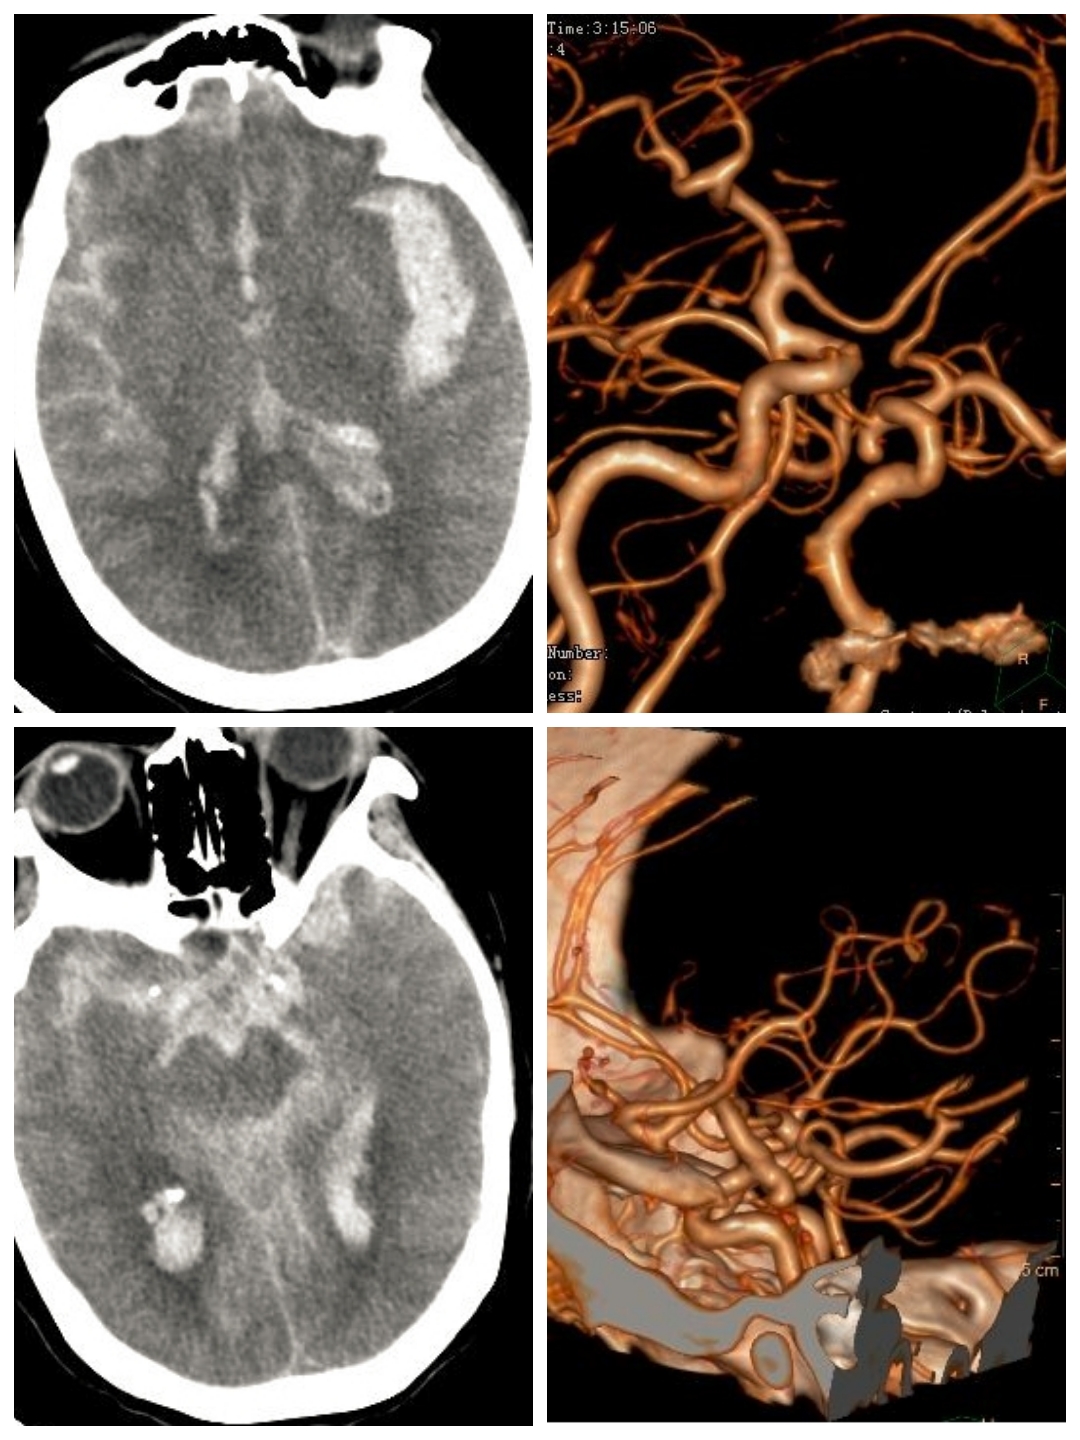

吴某某,56岁,女性,因“右侧眼睑下垂一周”入院

查体:神志清,右眼瞳孔4mm,对光反射消失,右眼睑下垂

DSA提示右侧后交通动脉瘤,左侧颈内动脉末端动脉瘤,左侧后交通圆锥,左侧海绵窦夹层动脉瘤。

下面这个动脉瘤像不像一颗爱心,可是它很“凶残”。随时可能破裂出血,危急患者生命。

我们术中先解决右侧后交通责任动脉瘤,再解决左侧颈内动脉末端以及海绵窦夹层动脉瘤,手术顺利,动脉瘤消失,可谓一箭三雕🐮!